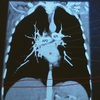

Q

Describe el perfil cardiaco